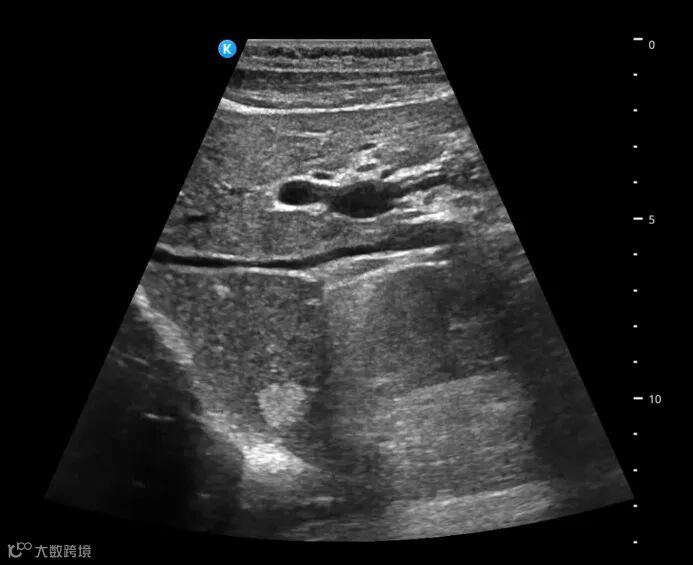

深圳鲲为科技有限公司是以突破性原创技术引领,并致力于下一代超分辨超声开发的专业影像设备公司。